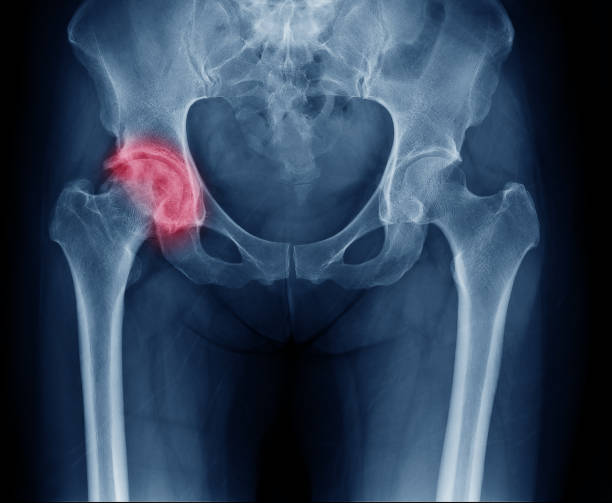

고관절 통증 원인-부상

고관절 통증은 부상에 의해 발생할 수도 있습니다. 스포츠나 사고로 인한 고관절 관련 부상은 통증과 함께 발생할 수 있으며, 시간이 지남에 따라 통증이 지속될 수 있습니다. 부상을 받게 되면 신속하고 적절한 치료를 받아야하며, 전문적인 재활치료를 통해 고관절을 회복시켜야 합니다.